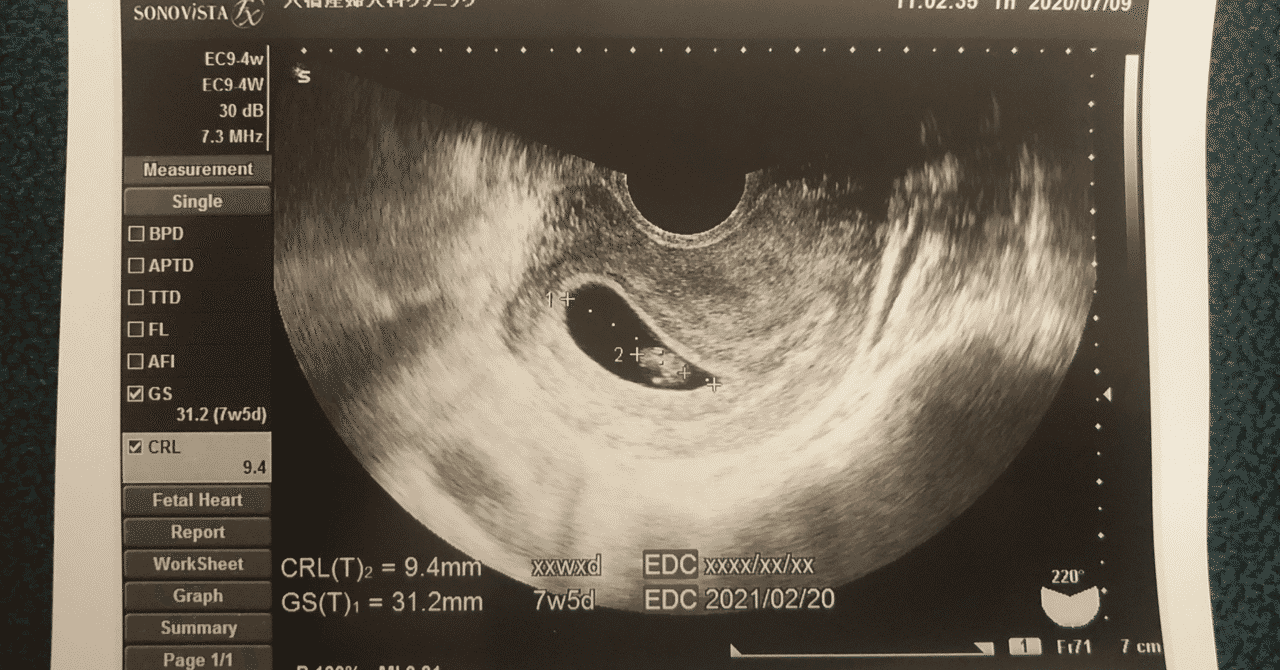

妊娠7週 写真

妊娠7週5日 7w5d の超音波 エコー 写真

妊娠7週 写真. 青枠が妊娠何週目かを表す部分、この写真は7wやから7週目を指しとるわけや。 黄色枠で囲った部分が 赤ちゃんの大きさ やで! 10.8mm 、ようは1センチくらいや。まだまだ小さいわ。 妊娠9週目のエコー写真(胎児の大きさや状態). 妊娠7ヶ月(27週)のお腹 妊娠7ヶ月に入り、さらにお腹のカーブが大きくなりました。 この写真は7ヶ月に入ってすぐの写真ですが、月の後半から一気に妊婦感が増してきます。 この頃から、ひどい腰痛に悩まされるようになりました。 妊娠8ヶ月(31週)の. 妊娠8週の赤ちゃんの特徴 妊娠3ヶ月の第1週である「妊娠8週」は、妊娠初期も半ばを過ぎたころにあたります。 このころの赤ちゃんはどのように育っているのかをみていきましょう。 赤ちゃんはどのくらいに成長しているの?.